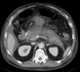

Pancreatic fat necrosis